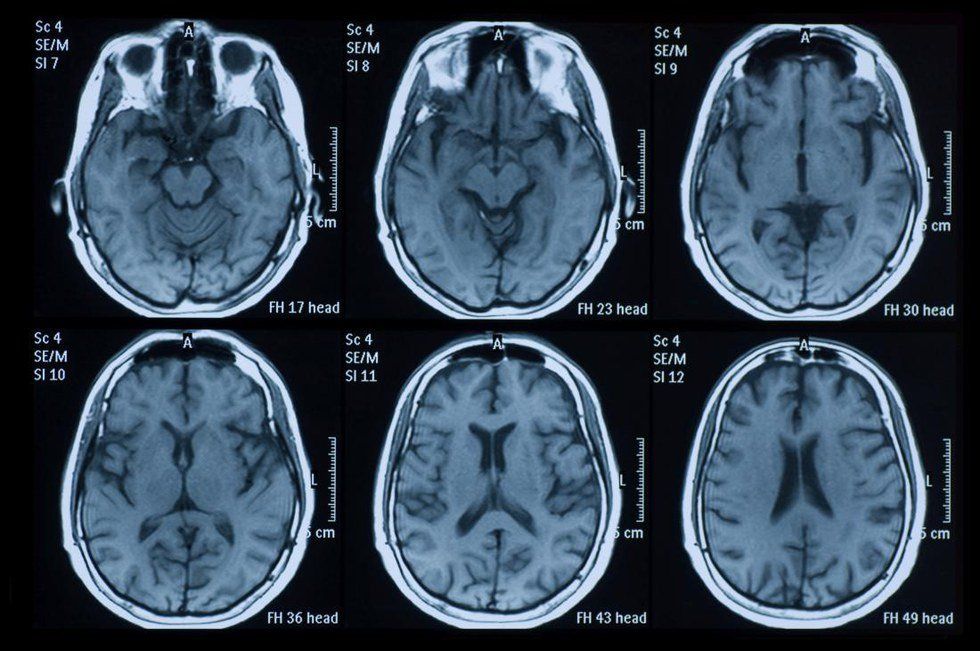

What exactly is Multiple Sclerosis? MS is a degenerative neurological disease. The disease causes the immune system to attack the myelin sheath that covers the nerve fibers, which causes problems sending signals between the brain and the body.

MS destroys a person physically, mentally and emotionally. It physically attacks your body by destroying nerve endings, eating away at muscles and making you physically tired. It attacks your brain; making it difficult to remember, causes mood swings and takes away from problem-solving skills. Emotionally, MS sends you on a roller coaster. Mood swings are common and it often leads to depression.